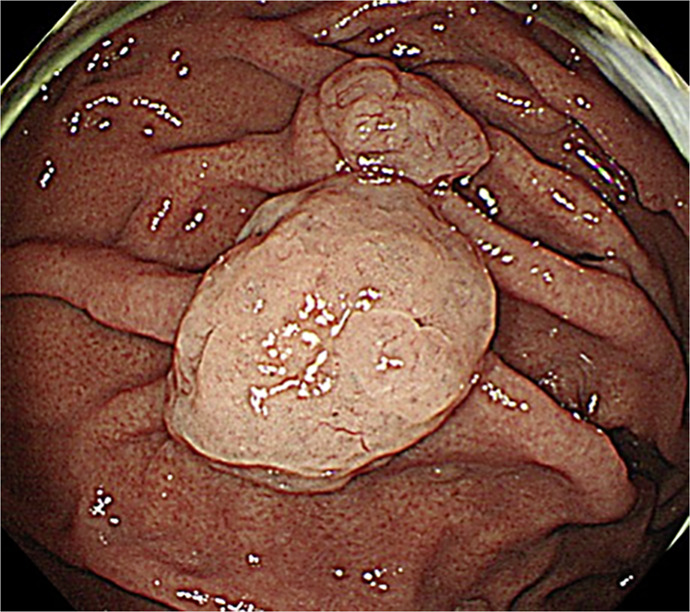

Case presentation: A female patient in her 60s had been taking PPI for reflux esophagitis for >10 years. An upper gastrointestinal endoscopy revealed two gastric polyps measuring 20 mm and 10 mm. She was referred to our hospital for resection, but narrow-band imaging revealed a nonneoplastic lesion. PPI was discontinued, and step-down therapy using vonoprazan was performed. During the treatment, a lifestyle guidance app (Muneyake PRO) was used to record daily heartburn symptoms, oral medication status, and daily life status. She was worried that her symptoms would worsen due to discontinuation, but she gained her understanding when the use of the app to monitor her symptoms was explained. The app was useful for understanding the progress of symptoms and the status of oral medication. Step-down therapy was performed only twice after PPI discontinuation, symptoms have not worsened, and follow-up endoscopy revealed significant gastric polyp shrinkage.

Conclusion: We experienced a case in which minimal acid-suppression treatment and step-down therapy using vonoprazan resulted in GERD symptom control and significant gastric polyp shrinkage.